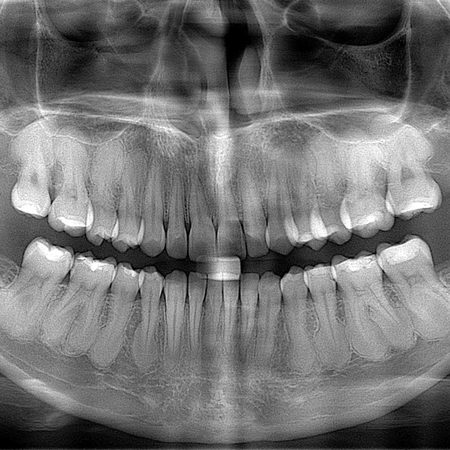

Hipercementose: os dentes podem ou não ser movimentados?

INTRODUÇÃO: O tipo mais frequente de hipercementose, quando moderada ou intensa, deixa o dente com a forma de clava. Nesses casos, não se deve movimentá-lo ortodonticamente, pois o formato da raiz dificulta ou impede a ação de forças no ligamento periodontal, que induziria os mecanismos biológicos da movimentação osteodentária. METODOLOGIA, RESULTADOS E DISCUSSÃO: Para diagnosticar se a hipercementose em forma de clava é moderada ou intensa, o critério proposto é traçar uma...

Hypercementosis: can teeth be moved or not?

INTRODUCTION: The most common type of hypercementosis, when moderate or severe, leaves the tooth in the shape of a club. In these cases, orthodontic movement should not take place, as the shape of the root hinders or prevents the action of forces on the periodontal ligament that would induce the biological mechanisms of osteodental movement. METHODOLOGY, RESULTS AND DISCUSSION: To diagnose whether club-shaped hypercementosis is moderate or severe, the proposed criterion is to draw a tangent...